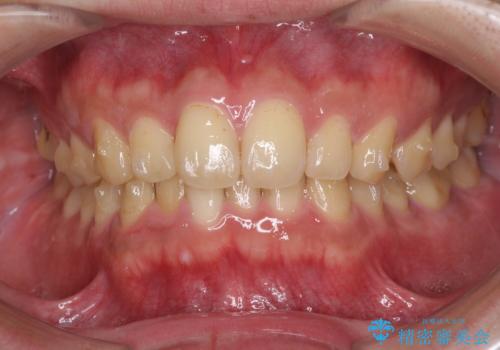

- 上下前歯のデコボコと下の前歯が隠れるほどの深い咬み合わせを気にして来院された患者様です。

インビザラインによる上下歯列の拡大と、IPR(歯と歯の間を削る)にるスペースの獲得により、口元のデコボコとディープバイトを改善することとしました。

デコボコがなくなったことで日頃の清掃が行いやすくなり、深い咬み合わせが改善したことで、食いしばりによる顎の負担も軽減されました。